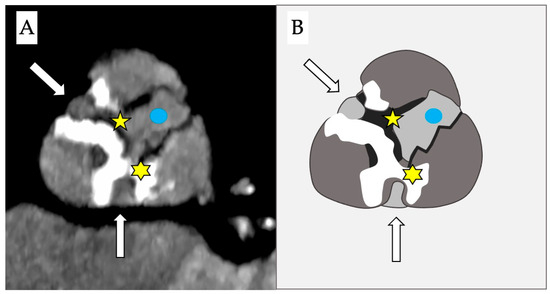

Stenotic disease of the aortic valve encompasses a wide range of anatomopathological variations, including the presence of fibrotic or calcific bridges between the cusps (Figure 2) that could allow passage of a guidewire through a lateral orifice.

Figure 2.

Computed tomography (A) and schematic figure (B) of a stenotic aortic valve that depicts the presence of 2 simultaneous bridges: one fibrotic between the right and the non-coronary cusps (yellow star) and a second calcific bridge between the left and the non-coronary cusps (yellow asterisk). This creates two anomalous new orifices (white arrows) where the guidewire can pass through and which are distinct from the true anatomical orifice (blue dot).